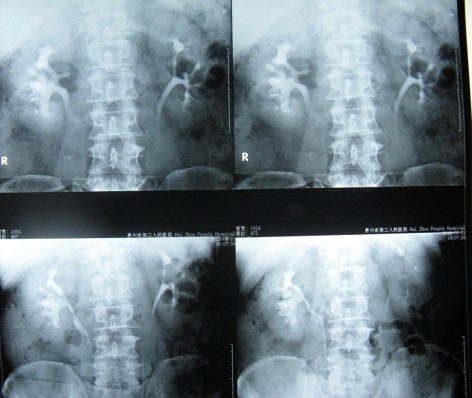

2 术前肾静脉造影可以看到右肾无积水